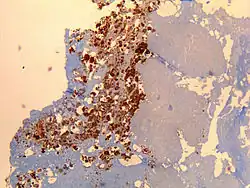

Immunohistochemical detection of C. burnetii in resected cardiac valve of a 60-year-old man with Q fever endocarditis, Cayenne, French Guiana: Monoclonal antibodies against C. burnetii and hematoxylin were used for staining; original magnification is ×50. | |